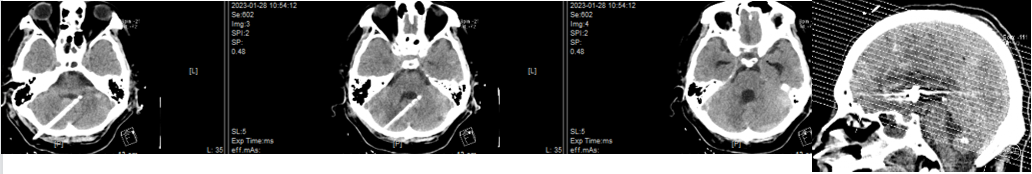

急诊头颅CTA:前交通动脉瘤

麻醉后先双侧侧脑室钻孔置管,夹闭引流管,接台行前交通动脉瘤栓塞。右侧A1发达,但是右侧入路动脉瘤显示不佳。

左侧入路显示效果可,但左侧A1纤细,三套微管通过危险系数高。

DSA示前交通动脉可见约12.4mm×7.6mm大小动脉瘤,瘤颈宽6.9mm,瘤顶可见大小约2.8mm×5.2mm的子瘤。